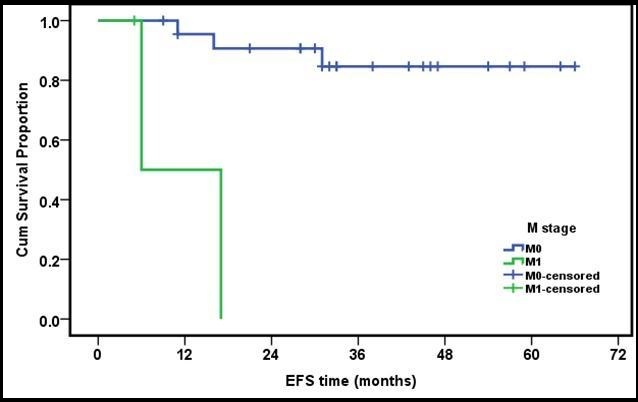

The OS for early stages (T1 and T2) was 100%, T3 (87%) while T4 cases were 72.7% with no statistical significance (p value =0.2). Similarly, OS for N0,1 was 88.8%, and for N2,3 82.3%, again with no statistical significance (p=0.39). On the other hand, OS for M0 was 91.3% and for M1 33.3% with statistical significance (p =0.032)( Figure 3 and Figure 4).

Figure 4.3 years EFS of metastatic versus non metastatic group of patients

Twenty-three patients (88.4%) in the present series were stratified as M0, while 3 patients (11.6%) were M1. Their OS survival was 91.3% versus 33.3%. This was the only prognostic factor identified in our study.

In our study, the presence or absence of distant metastasis at presentation was found to be the only factor of statistical significance. Similar finding was reported by many other authors who reported age and sex having no prognostic significance20, 21, 24. Good responders to neo-adjuvant chemotherapy were found to have a better OS and EFS in some studies 20, 22, 25, 30, while others -including the present study showed no statistical difference according to initial response 21, 24, 26, 27.